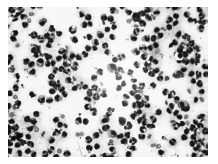

В цитограммах большинства больных, получив-ших ЛТ, выявлено снижение количества полиморфноядерных нейтрофилов и их дегенеративных форм с заметным повышением количества лимфоцитов к 4-ому дню. На фотографиях цитограмм отображены наиболее характерные изменения клеточного состава при адекватных дозах лазеротерапии на 2-ой и 4-ый день (рис 3,4).

рис.4. Адекватная ЛТ, 4ый день

Видно снижение количества всех исследуемых клеточных элементов на 4-ый день. Эти цитологические изменения являются проявлением угнетающего действия лазерного облучения. На фотографиях цитограмм отображены наиболее характерные изме-нения клеточного состава при передозировке ЛВ на 2-ой и 4-ый день (рис.5,6).

рис.5. Передозировка ЛВ, 2-ой день

рис.6. Передозировка ЛВ, 4-ый день